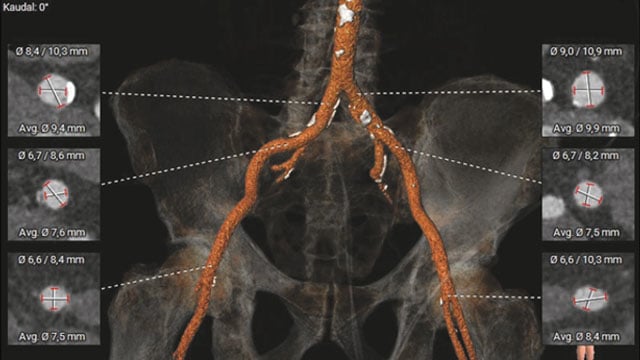

A challenging valve-in-valve scenario in a patient with prior aortic coarctation repair

A 79-year-old with a degenerated aortic bioprosthesis after complex coarctation surgery challenges conventional strategies. Which access route would you choose?